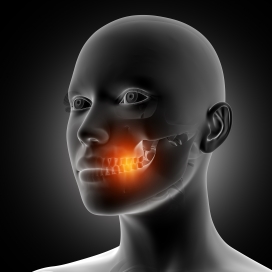

一张嘴就臭味袭来?怎么刷牙都没用?可能是这3种疾病的信号尽管遵循良好的口腔卫生习惯通常可以减轻口臭,然而有时候,即使经过刷牙等措施,仍难以彻底解决这一问题,这可能归因于其他潜在的健康因素或生活习惯的影响。在本文中,我将从医学角度出发,探讨口臭可能与哪些疾病有关,并介绍如何有效地应对口臭问题。口臭的常见根源之一是牙龈...

有口臭是怎么回事?70%-80%的口腔异味都是单纯性口臭,主要由蛀牙和牙周病等口腔疾病引起。除了要积极治疗口腔疾病外,每天要勤刷牙,在刷牙时同时也刷刷舌头,这样能减少口臭。二: 肝臭味:急性肝炎如果在呼气时,或在观察尿液时,能闻到有类似烂苹果或烂鸡蛋的臭味,即是肝臭。患肝癌或急发性肝炎等...

牙齿表面的“小黄石”,又臭又脏?想要去除它,不妨试试这6招!它的存在也是口臭出现的原因。 所以我们一定要用正确的方式来去除,那么怎样做才能够达到这一效果呢? 1.白矾刷牙 白矾其实就是矿物质明矾... 若是没有清理干净,同样会影响口腔健康。 综上所述,所谓的牙齿表面出现的小黄石,其实就是牙结石,它的出现跟口腔清洁不到位有很大的关系,...